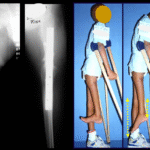

O tratamento consiste na ressecção do nicho central (fig. 5). Não é necessário remover toda a esclerose ao redor. Quando a falha óssea provocada na ressecção representar risco para fratura (como no colo do fêmur (fig. 6) deve-se colocar enxerto ósseo.